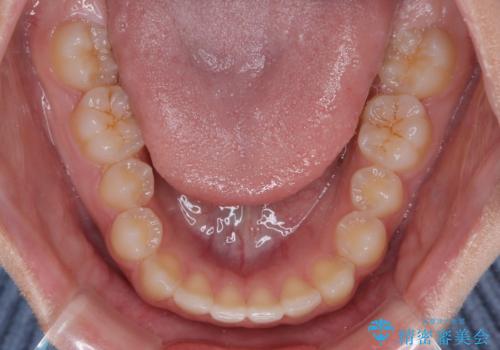

- 前歯の隙間を気にして来院された患者様です。

口元の突出感があり、小臼歯4本を抜歯して口元を引っ込める矯正治療も提案しましたが、本人は口元の突出感は気になっていないとのことで、インビザラインにて隙間やデコボコを改善することとしました。

軽度の歯列不正であったため、廉価版のインビザライン・モデレートパッケージにて治療を終えることができました。